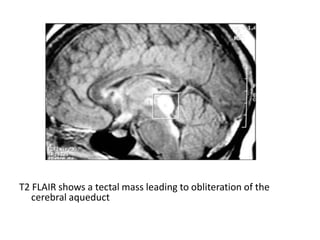

T2 FLAIR shows a tectal mass leading to obliteration of the

cerebral aqueduct

-MRI :

-Typically the tumors demonstrate expansion of the

tectal plate by a solid nodule of tissue

*T2 :

-Hyperintense to grey matter